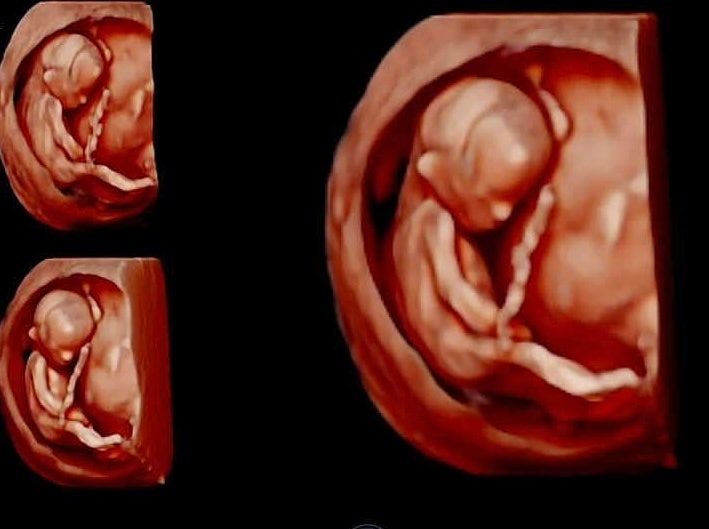

13주차 초음파 성별확인 공주님 feat. 입체 초음파 잘 찍는 팁

13주차 2일째 되는 날 1차 기형아 검사를 받으러 산부인과를 방문했답니다. 1차 검사는 11~13주 사이에 받...